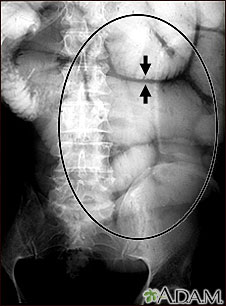

This abdominal x-ray shows thickening of the bowel wall and swelling (distention) caused by a blockage (pseudo-obstruction) in the intestines. A solution containing a dye (barium), which is visible on X-ray, was swallowed by the patient (the procedure is known as an upper GI series).